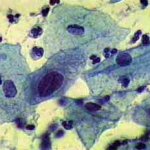

Δυσπλασίες τραχήλου μήτρας σοβαρού βαθμού (CIN III)

Ασυμπτωματική ασθενής 39 ετών. PH κόλπου 4,4. Κολποσκόπιση:

Στην δοκιμασία οξικού οξέως και στην δοκιμασία Lugol, αρνητική περιοχή, τόσο στο πρόσθιο, όσο και στο οπίσθιο χείλος του τραχήλου, σε ακτίνα 3-4 χιλ. και πλάτος περίπου 5 χιλ., με εικόνα διακριτικού επίπεδου μωσαϊκού.